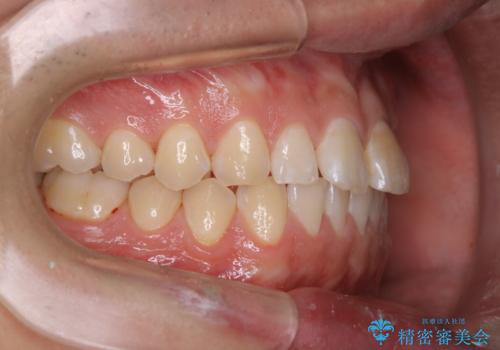

- 矯正治療を考えていて、歯科医院が久しぶりのためまずはクリーニングしたいとのことでした。PMTC60分コースを行いました。

今後、矯正を考えている場合は、まず現状の口腔内をチェックし、虫歯や歯周病などを早期に発見し進行を防ぐことが大切です。